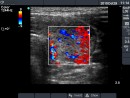

Ultrasonography: Both lobes were enlarged, moderately hypoechogenic, inhomogeneous and displayed increased vascularization.

Follow-up examinations (rows from 1st to 8th):

2. Note the relation between volume, echogenicity, vascularization and hormone levels.